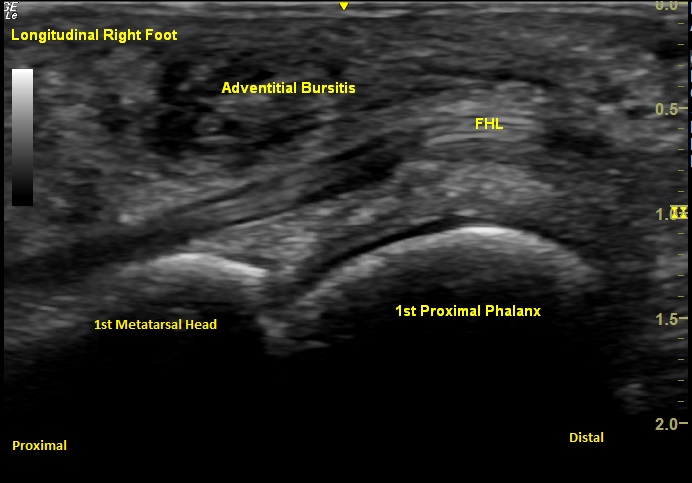

Labeled Long Axis view of the plantar first metatarsophalangeal joint demonstrating adventitial bursitis overlying the medial and lateral sesamoids with the intact flexor hallucis longus (FHL) tendon visualized in plane.